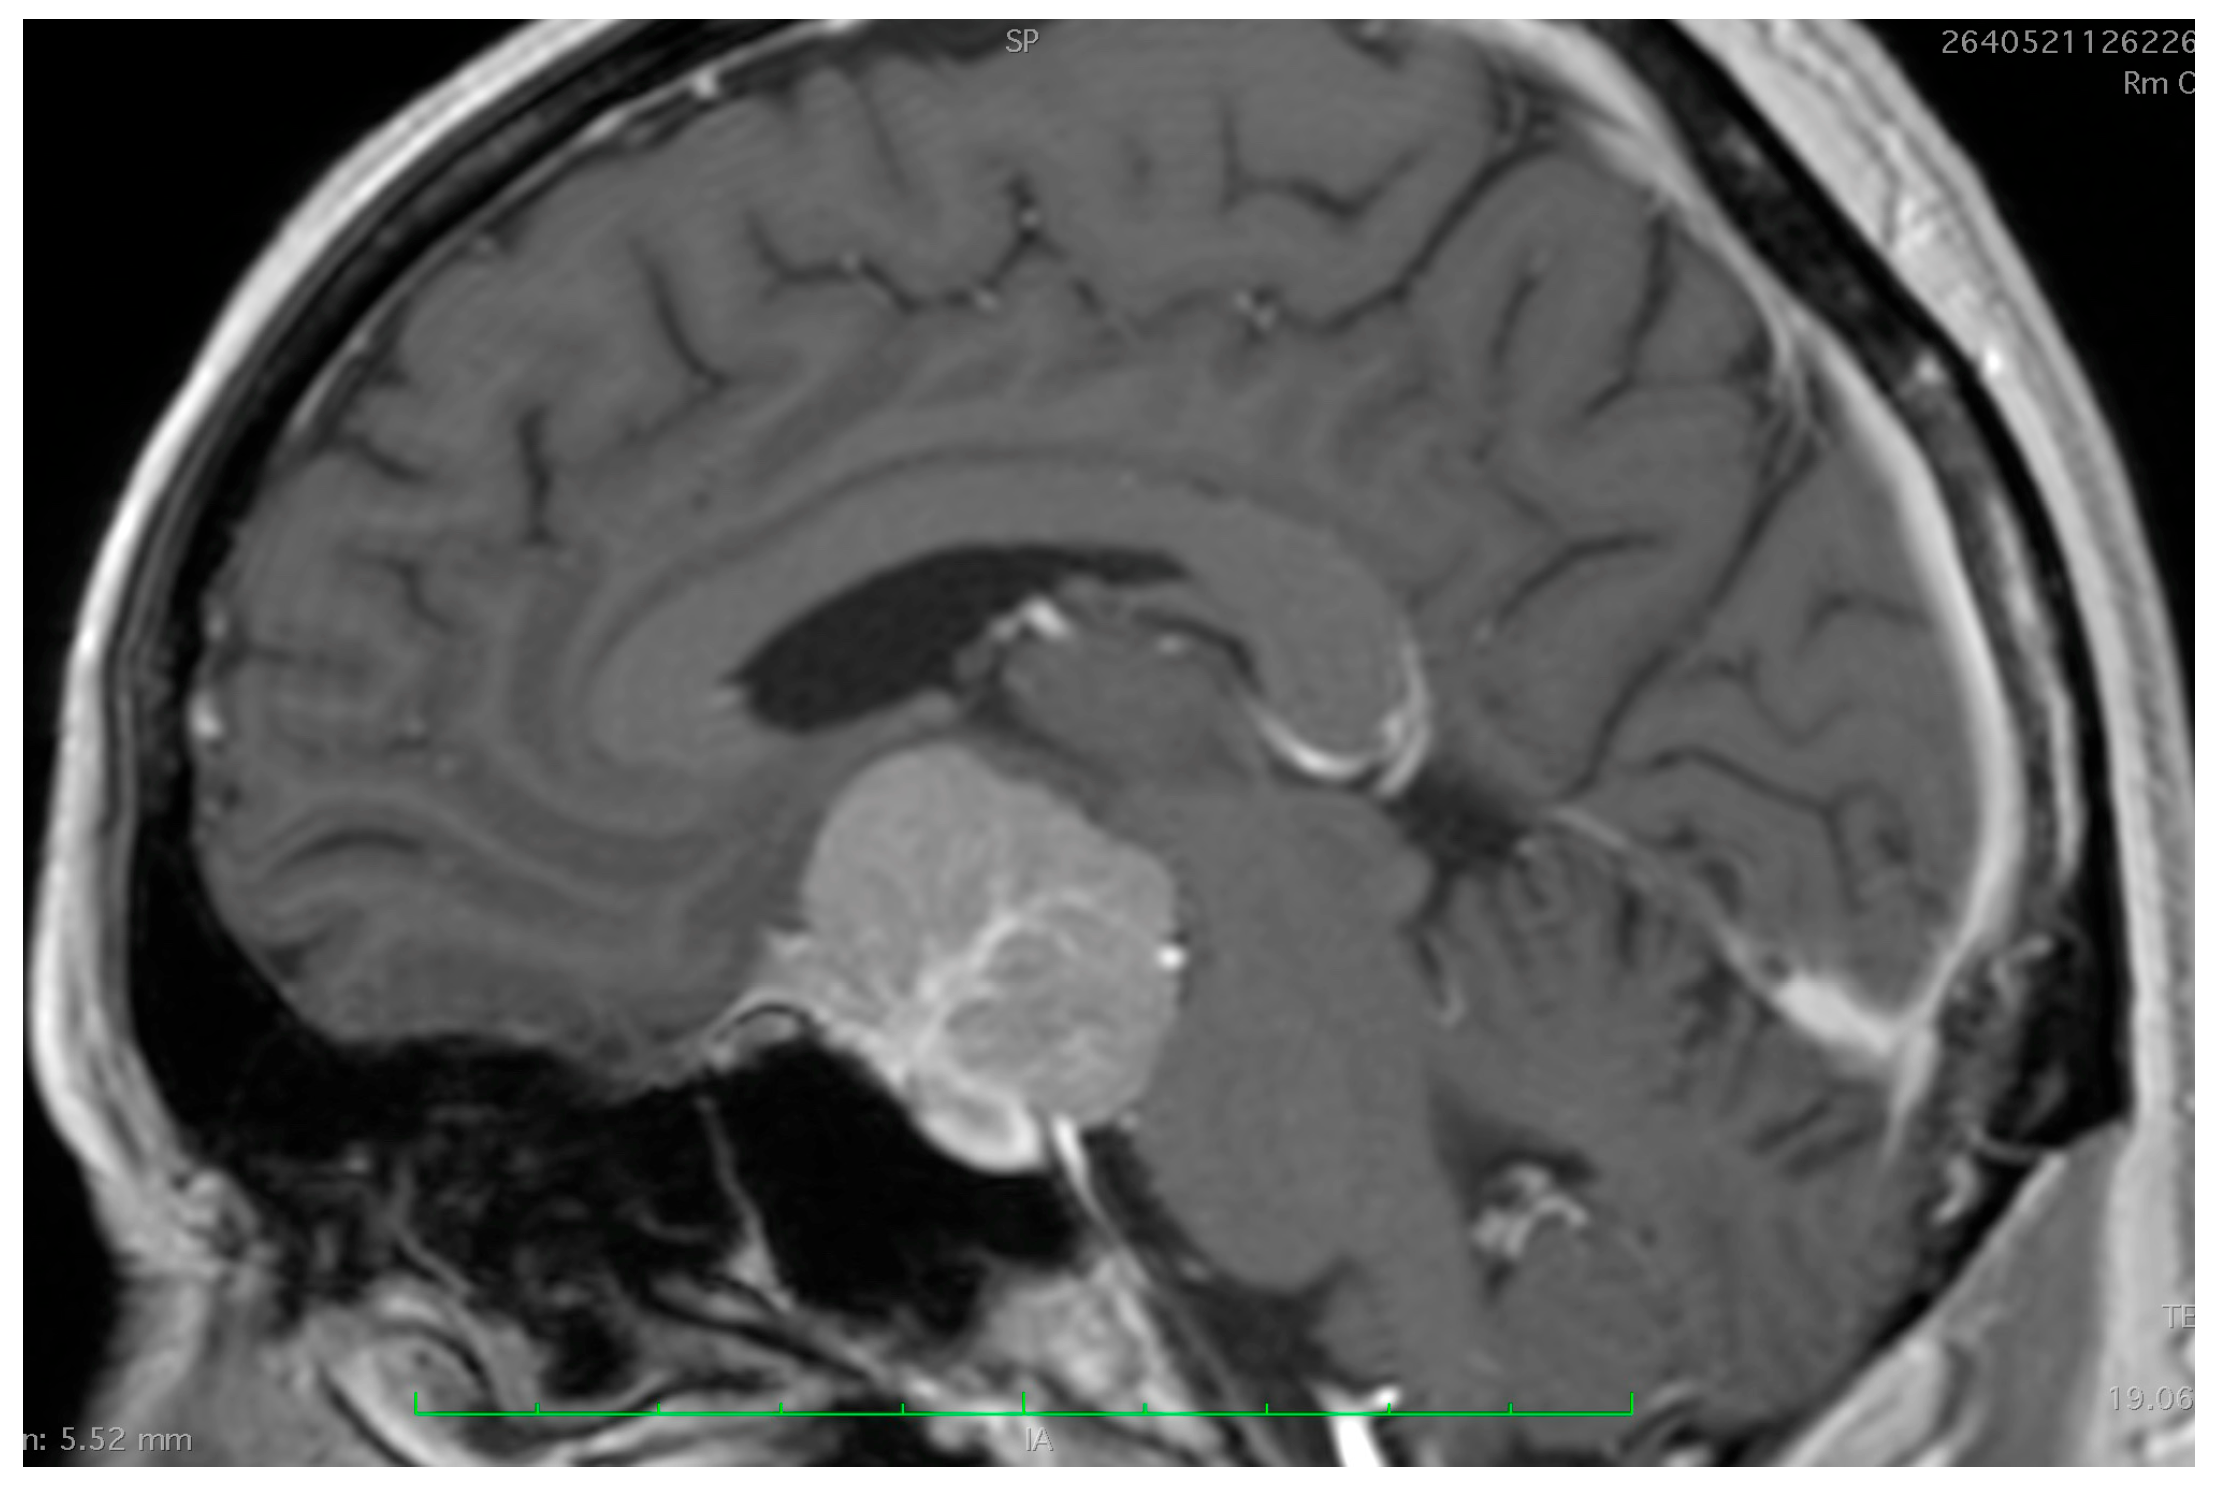

2. Assessment of Tumor Origin and the Presence of an Arachnoid Cleavage Plane

2.1. Surgical Significance

2.2. Imaging Evaluation

2.3. Key Surgical Considerations